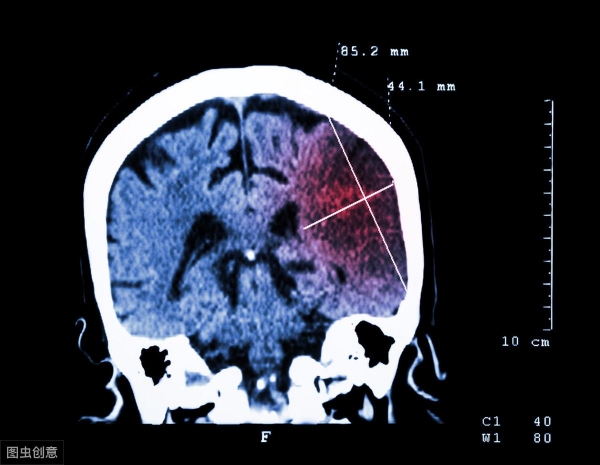

"脑供血不足"是指由于脑组织血液供应障碍而引起的一系列临床症状和体征。

近年来,脑供血不足的发病率越来越高,给患者的日常生活造成了很大的影响。